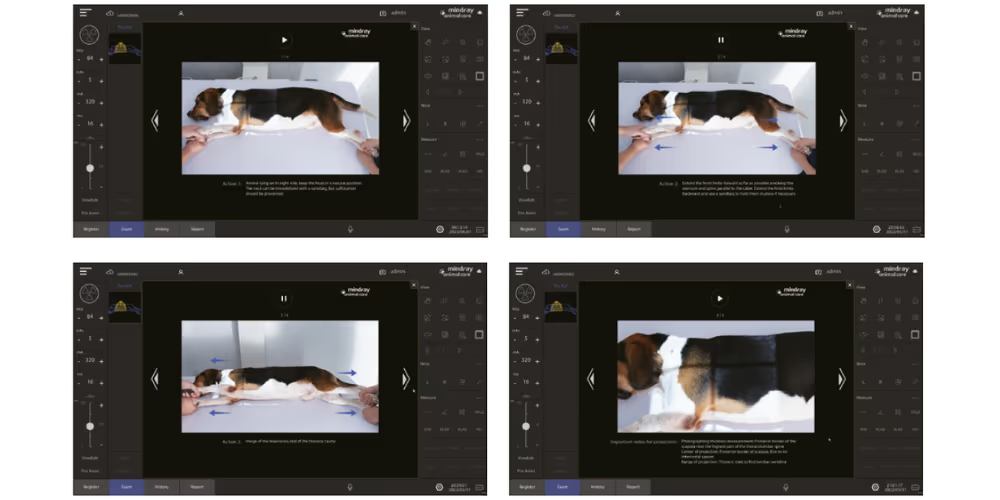

iShotHelper Profesyonel Konumlandırma Rehberi

iShotHelper Profesyonel Konumlandırma Rehberi

Detaylı yönlendirme ve doğru konumlandırma

Auto BTM

Otomatik Vücut Kalınlığı Ölçümü

Ses Kontrollü Pozlama

Etkin çekim sayesinde hayvanlar için kapsamlı bakım sağlayın

Karmaşık başlatma prosedürlerinin neden olduğu operasyonel hataların azaltılması